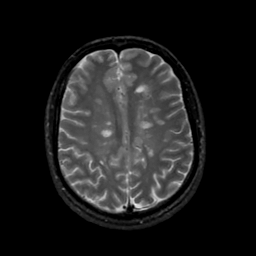

MR Study #17, July 7, 1991 -- Slice #34

[Home][Help][Clinical][Tour 1][Tour 2] Slice 34